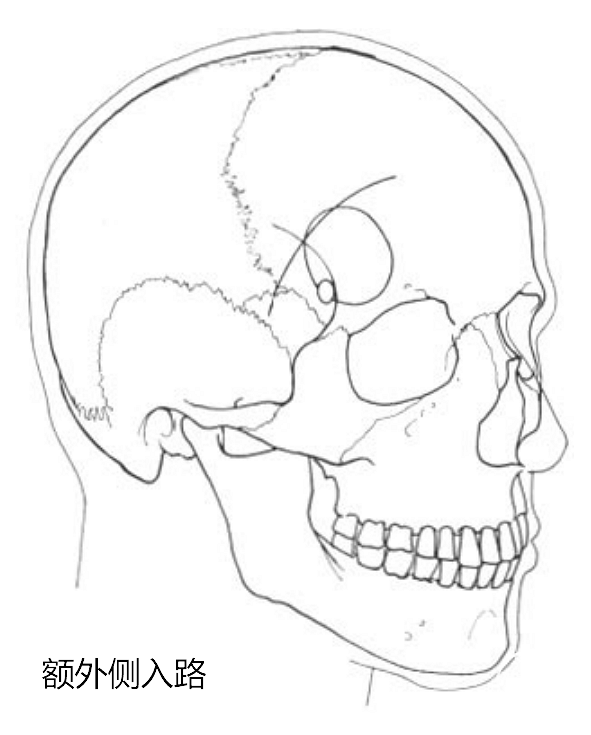

额外侧入路的艺术家视图。可见:额外侧入路是从前颅底外侧进入鞍区,并非直接沿着蝶骨嵴、外侧裂进入。